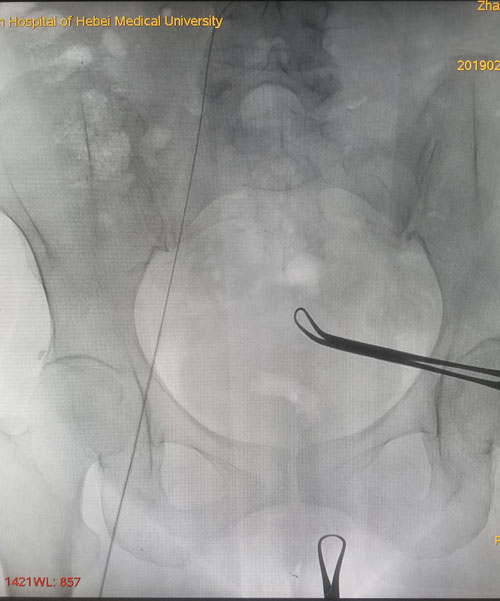

术中DSA评估导丝走形